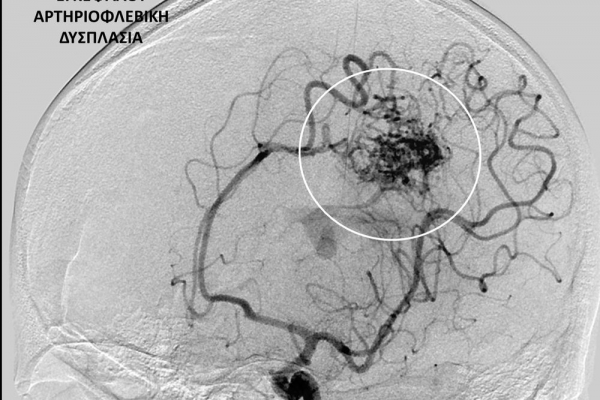

- Η ψηφιακή αγγειογραφία (DSA) αποτελεί την καλύτερη μέθοδο διάγνωσης των αγγειακών παθήσεων.Η αγγειογραφία γίνεται ως εξής: αρχικά παρακεντάται μια αρτηρία πρόσβασης, όπως η μηριαία αρτηρία στη βουβωνική περιοχή ή η βραχιόνια αρτηρία στο βραχίονα. Στη συνέχια προωθείται ένας καθετήρας προς την περιοχή του ενδιαφέροντος και γίνεται η έγχυση σκιαγραφικής ουσίας (σκιαγραφικού) με συνεχή λήψη «εικόνων» των αγγείων-στόχων.